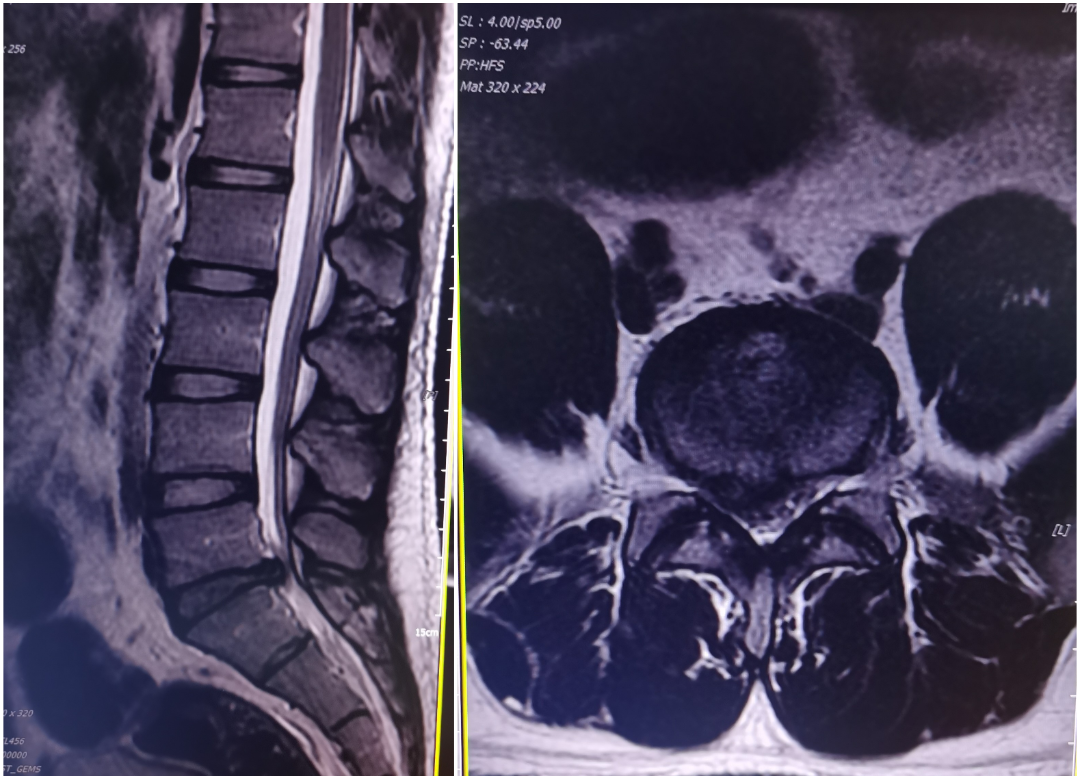

患者叶某,22岁男性,2月前劳动后出现腰部酸胀、麻痛,弯腰困难,站立行走、下蹲时明显,疼痛可向右大腿及小腿后侧及足底放射,平躺休息后缓解,症状反反复复,双下肢肌力感觉基本正常,结合辅助检查,诊断:腰5/骶1椎间盘突出,于局麻下行椎间孔镜下腰5/骶1椎间盘髓核摘除+神经根松解术,术后患者腰背部、右下肢无明显疼痛,术后第一天佩戴腰围下床自由活动。

术前CT、MR示:腰5/骶1巨大椎间盘突出